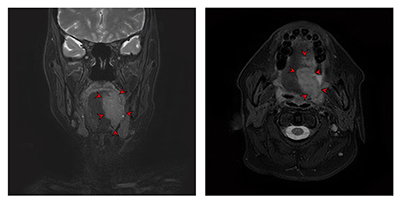

자기공명영상법(MRI)

전산화단층촬영(CT)과 더불어 임상적 병기 결정을 위한 정보를 얻는데 사용합니다. 연조직에 발생한 암종의 경우 자기공명영상이 더 선호되고 있어 설암 환자의 경우 자기공명영상이 필수적이라 할 수 있습니다. 촬영 전 구강 내 보철물은 제거하고 촬영하는 것이 상의 왜곡을 막기 위해 필요합니다.

좌측 설암의 자기공명영상 촬영 이미지

[좌측 설암의 자기공명영상 촬영 이미지]